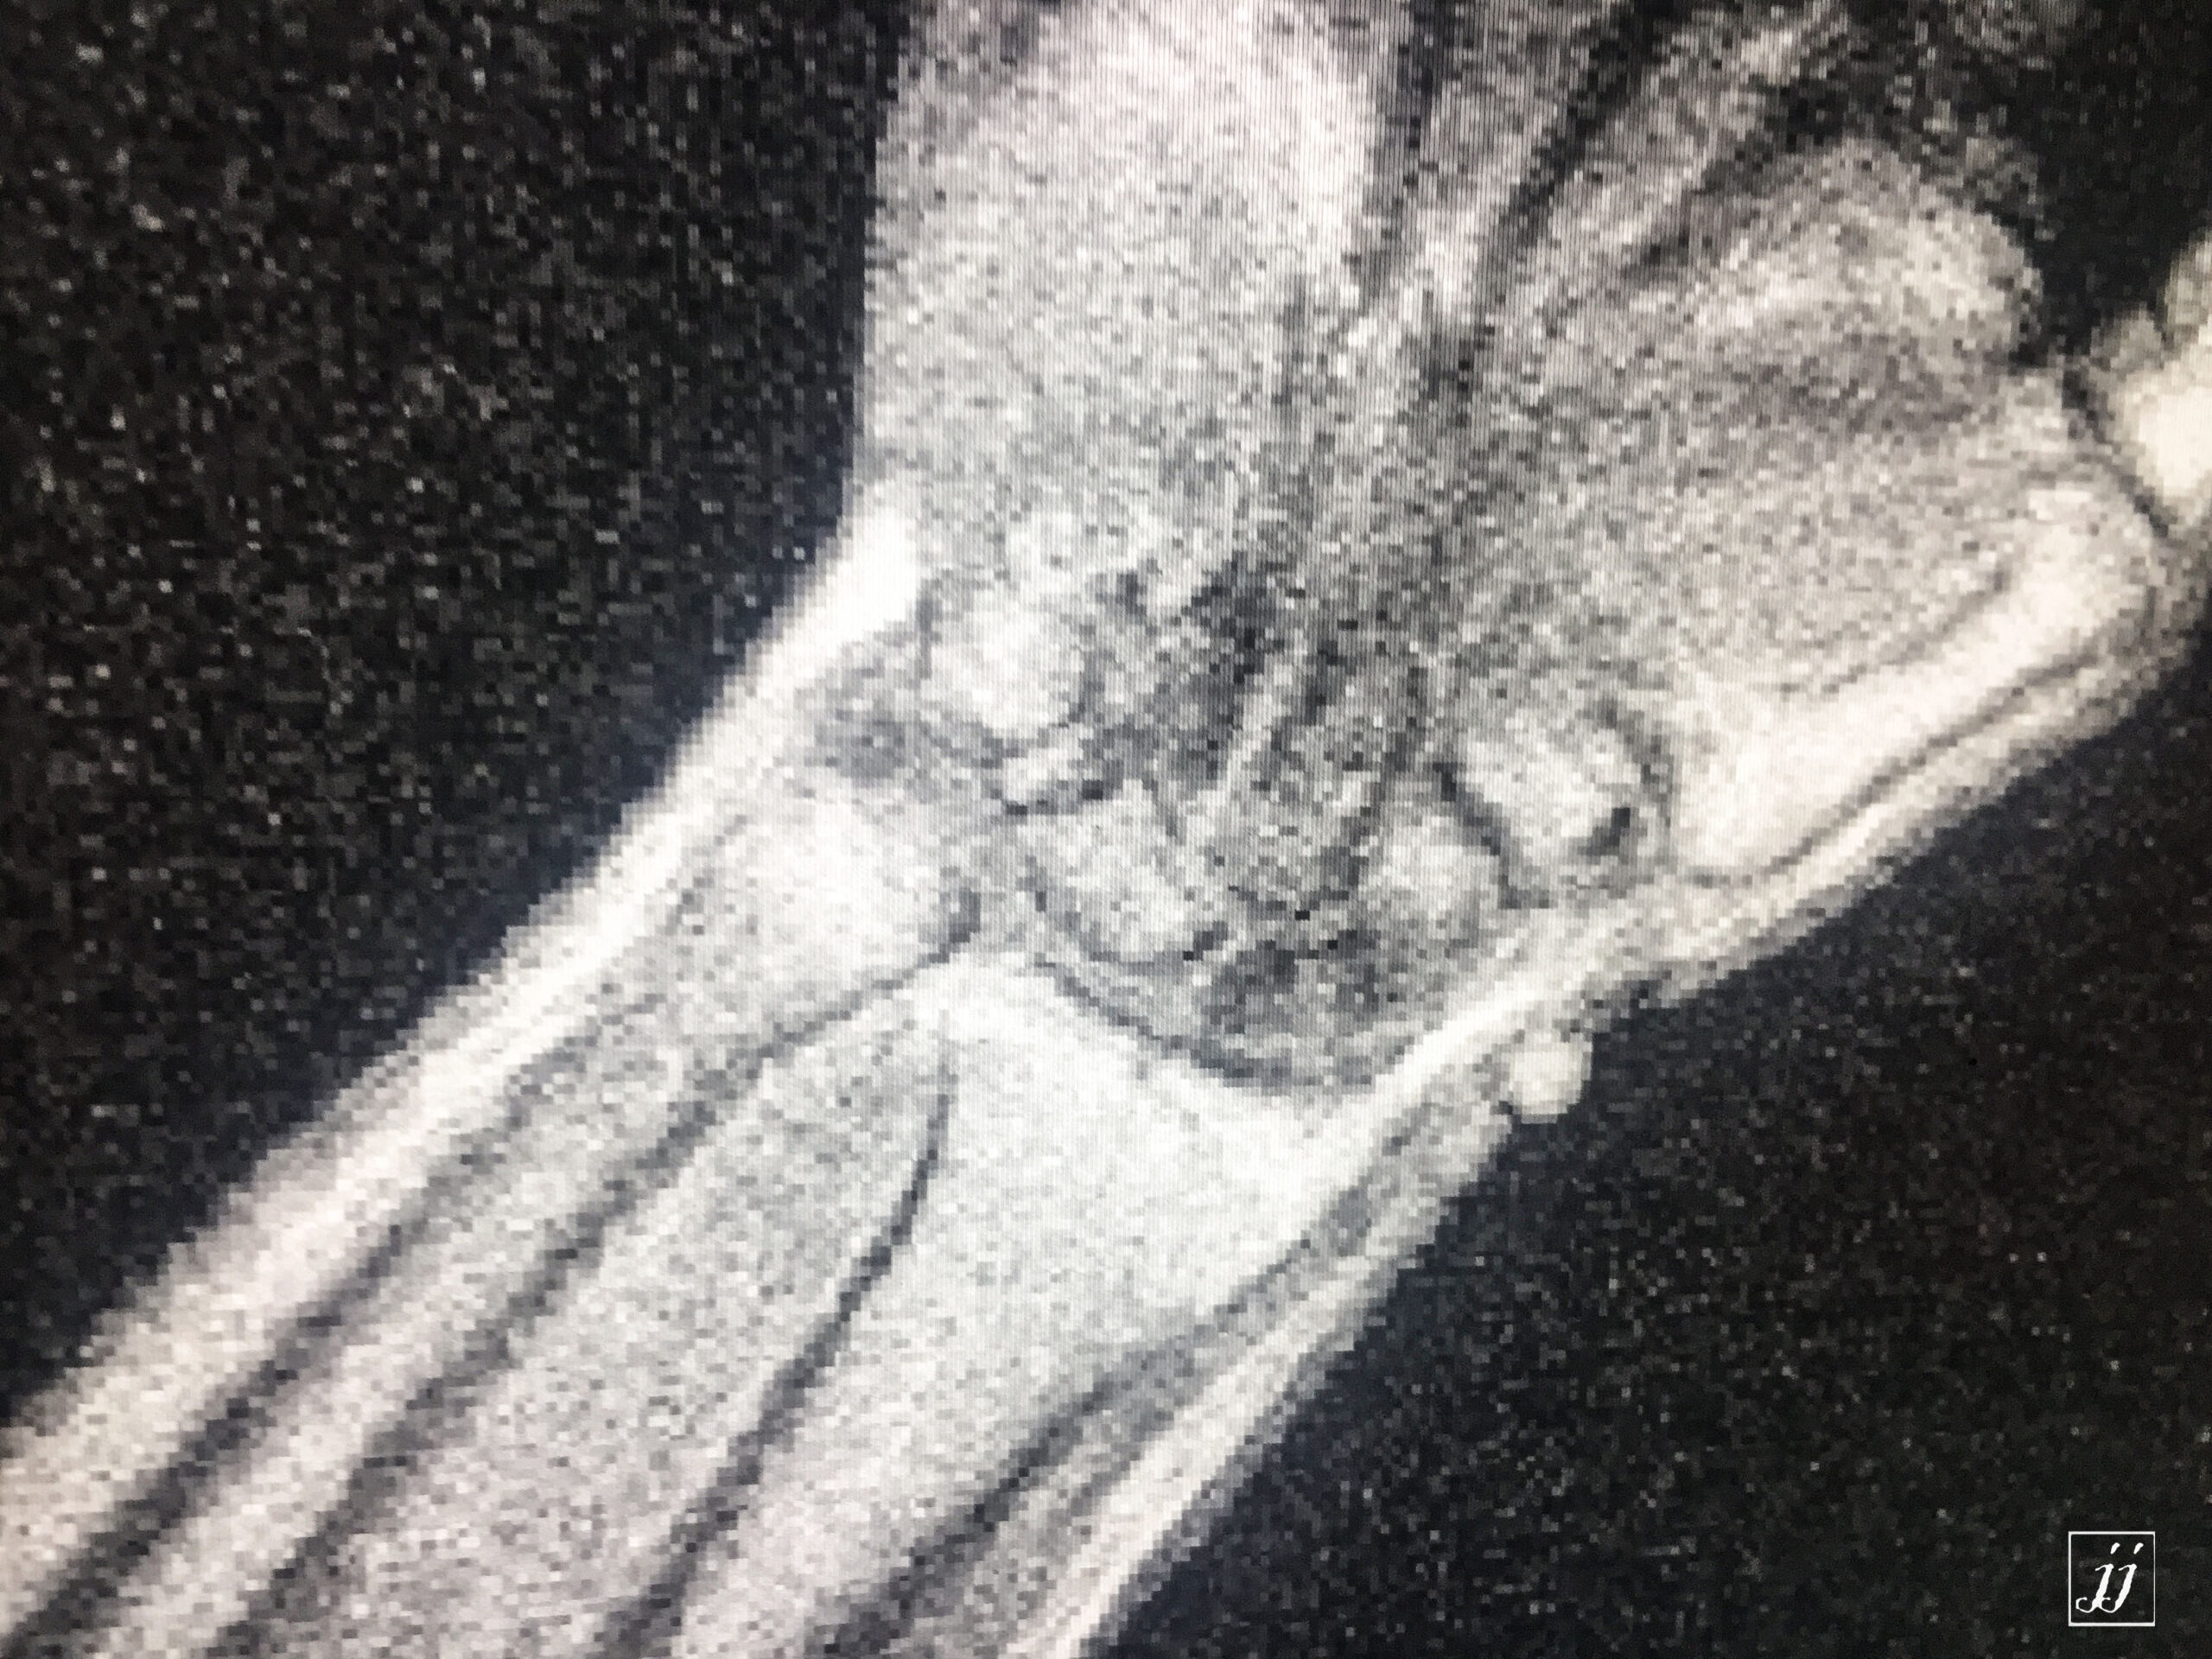

MSK- scaphoid fracture and proximal aVN (13)